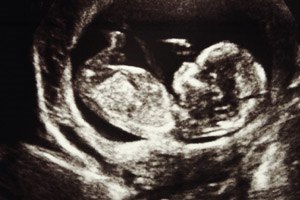

הגעת לבדיקת אולטרסאונד, לבירור מצב העובר - והתברר כי נמצאה...